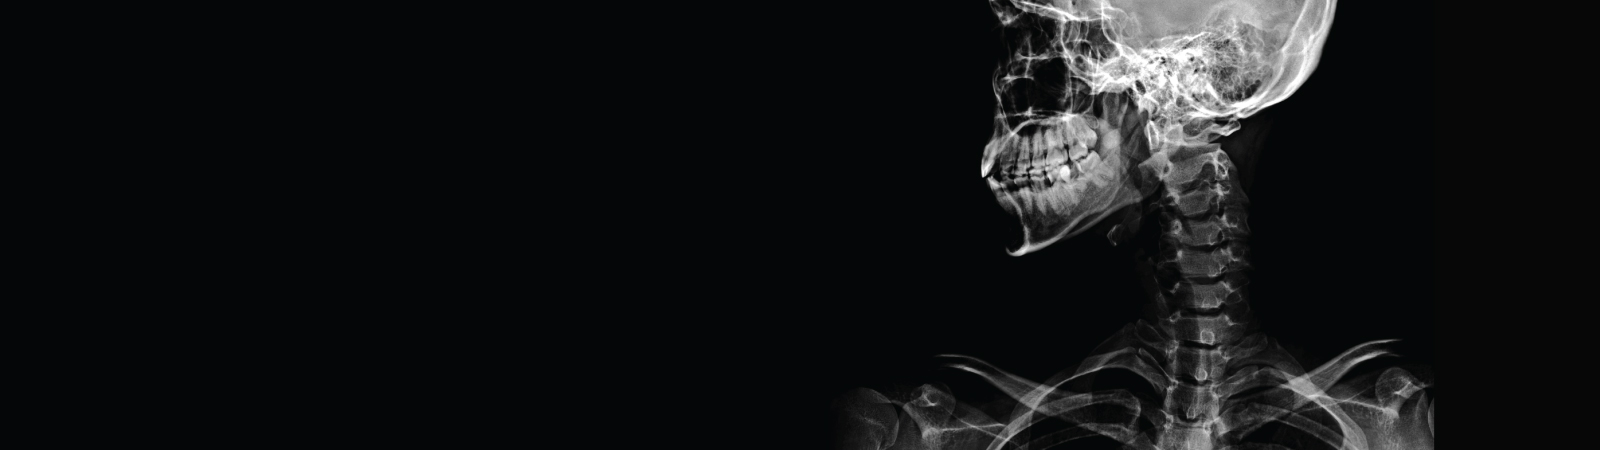

Community Health Partners offers an extensive range of healthcare services to care for you and your family at every stage of life. From simple check-ups to complex neurosurgery – and everything in-between – we’ve got you covered.